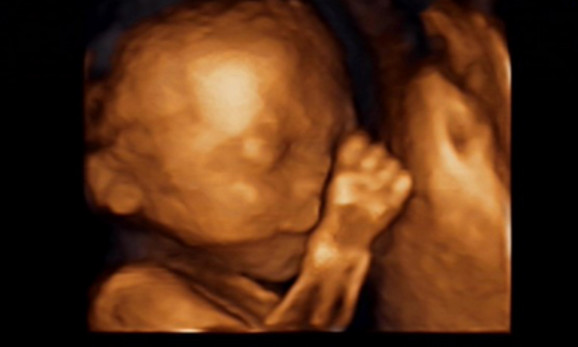

27岁的曹女士,已经怀孕六个月了。三天前,“孕味十足”的她,在丈夫的陪同下来到医院,准备进行提前预约好的四维彩超检查。但是万万没想到,检查结果让她的心情一下跌入低谷!通过影像显示,胎儿嘴唇中间竟然有一指宽的裂痕。经过医生再次仔细确认,腹中的胎儿确实患有唇腭裂,也就是“兔唇儿”。